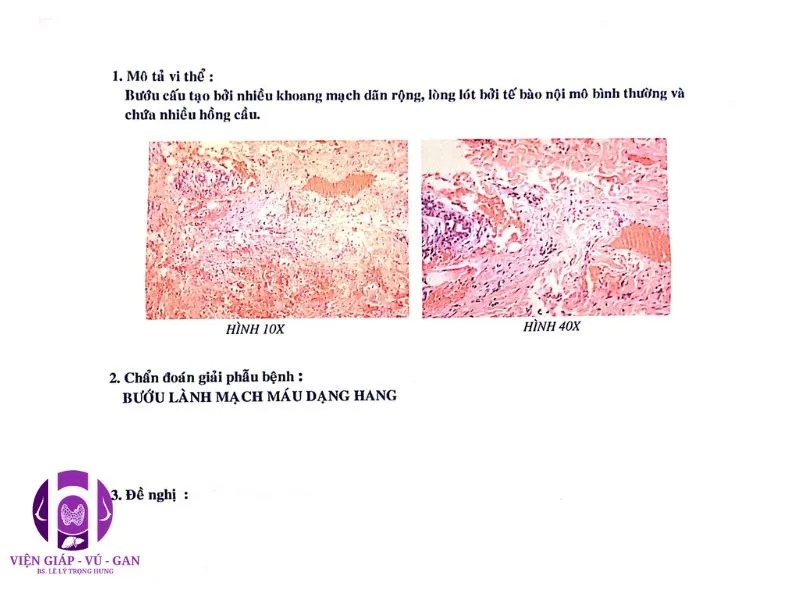

KẾT QUẢ GIẢI PHẪU BỆNH: Bướu cấu tạo bởi nhiều khung mạch máu giãn rộng, lòng lót tế bào nội mô bình thường và chứa nhiều hồng cầu.

- Kết luận : BƯỚU LÀNH MẠCH MÁU DẠNG HANG.